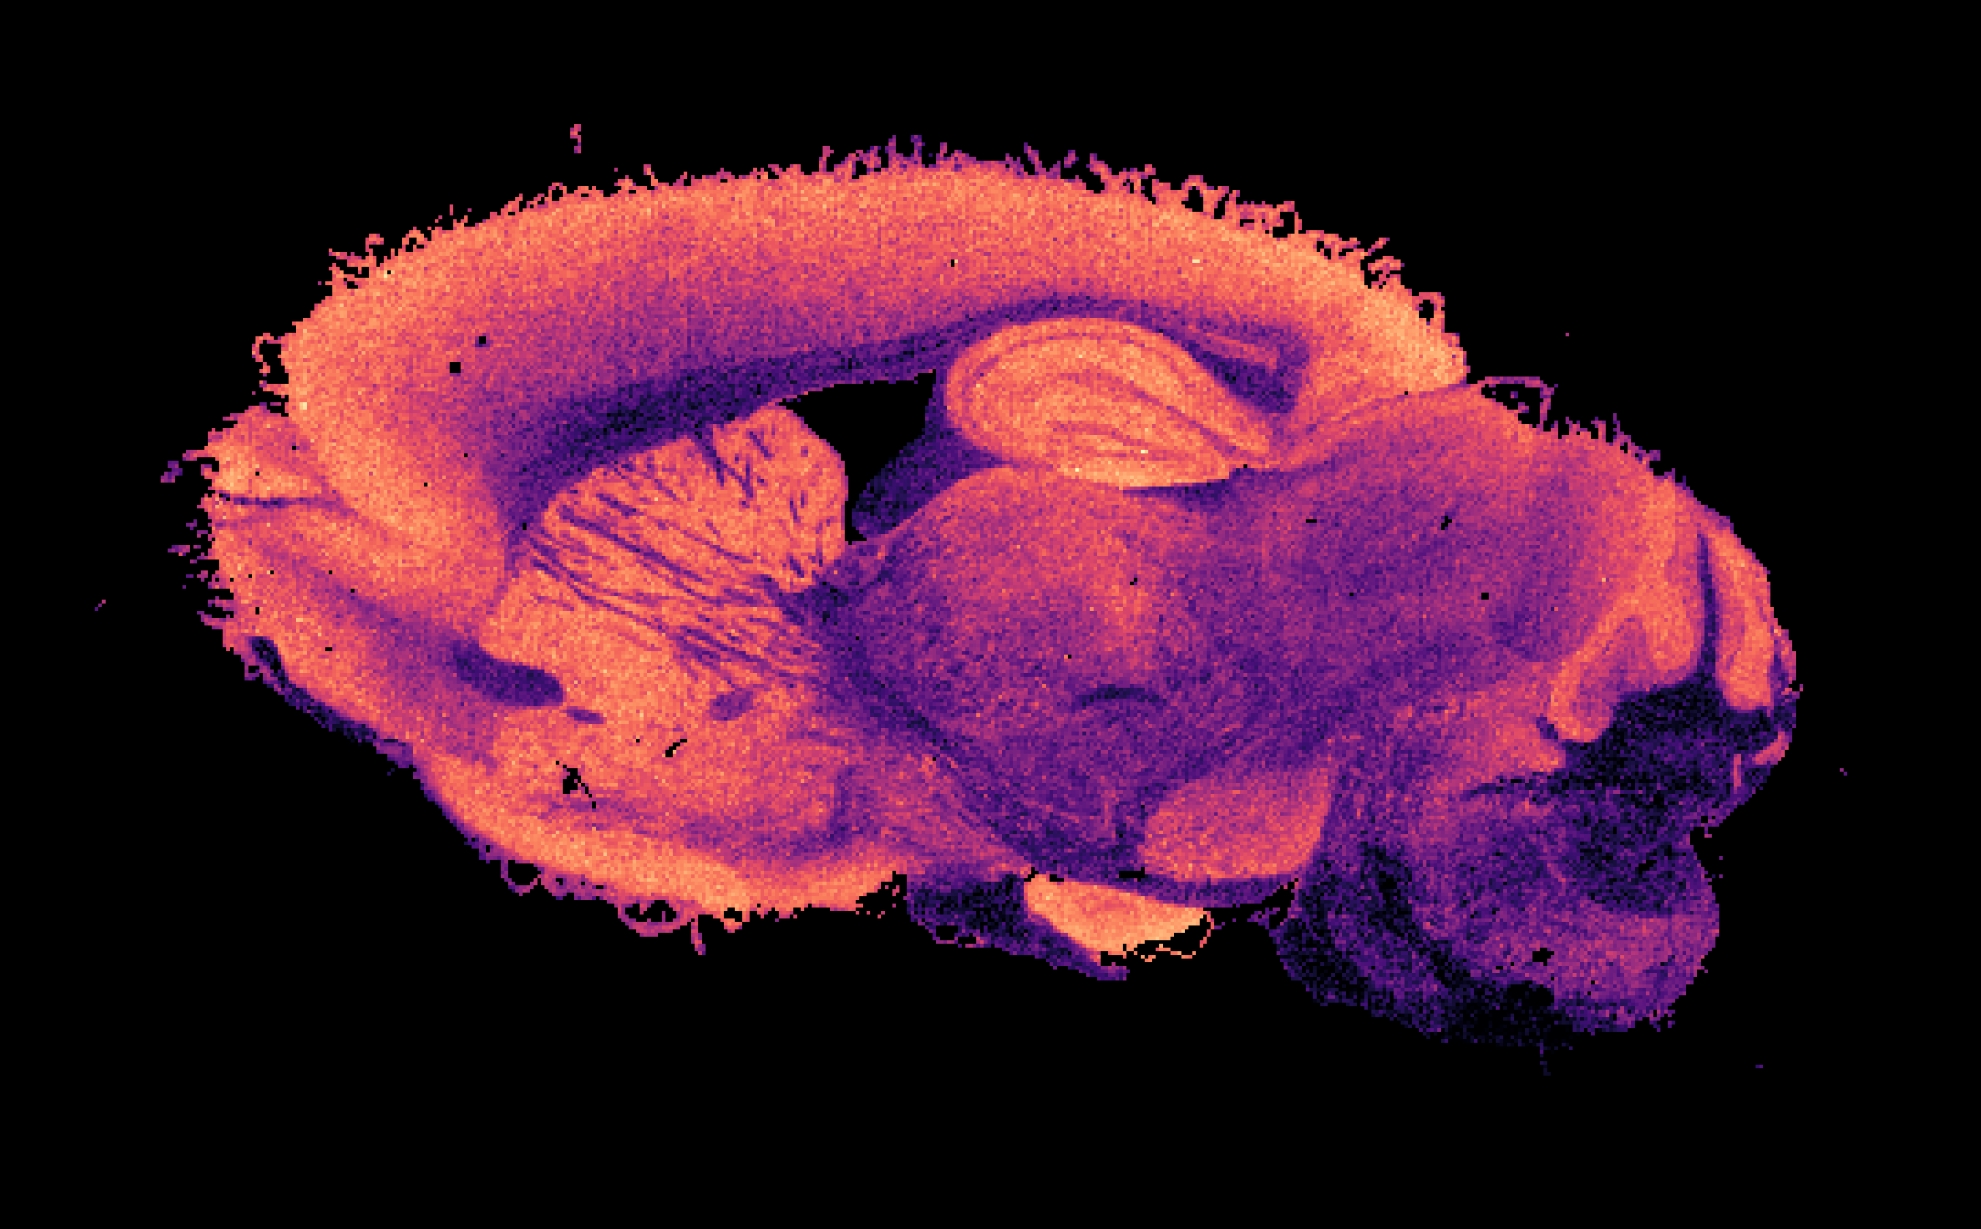

Picture of a slice of mouse brain in which a specific molecule is visible

Afbeelding van een plakje muizenbrein waarop een specifiek molecuul in kaart is gebracht

Nou kan door laboratoria van sommige ziekenhuizen, in het geval van een complexe vloeistof zoals een bloedmonster, al behoorlijk wat worden verteld over welke moleculen daarin voorkomen. Dit doen ze onder andere met behulp van massaspectrometrie beeldvorming. Daarbij wordt de massa van de moleculen gemeten, wordt gekeken hoeveel er van die verschillende massa’s aanwezig zijn en – in het geval van een stukje weefsel – waar ze precies zitten. Het resultaat daarvan zie je in de afbeelding boven dit artikel terug. Dit vertelt je alleen nog niet alles. Twee moleculen kunnen hetzelfde wegen, maar een hele andere functie hebben. Het is daarom ook nodig om iets te zeggen over de structuur van elke molecuul. Alleen dan weet je zeker met welke je precies te maken hebt.